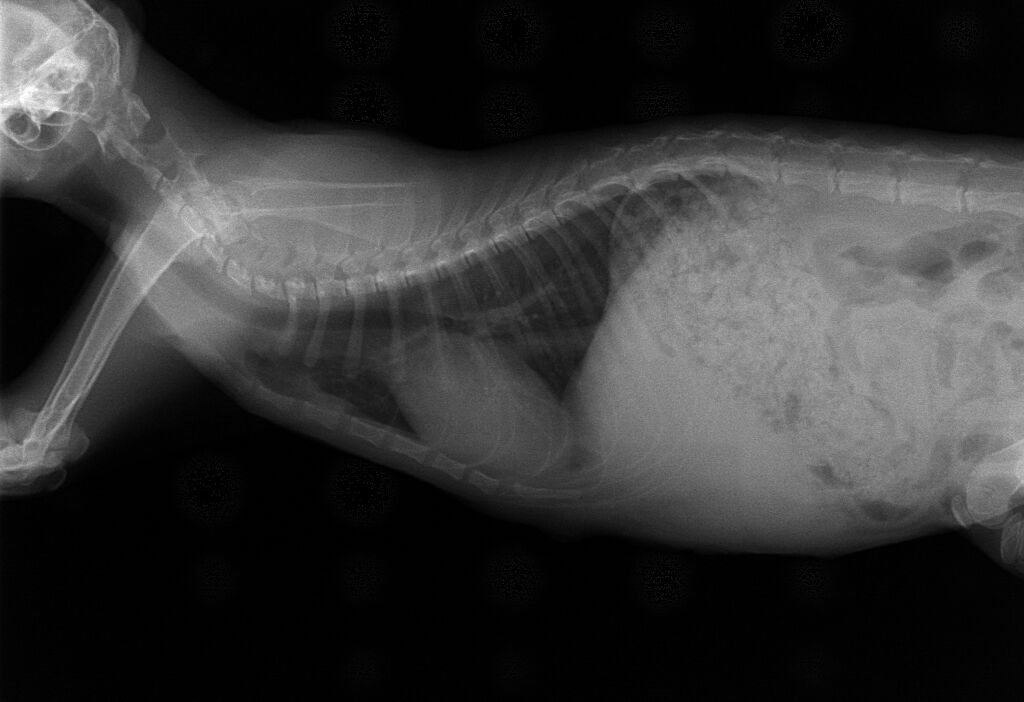

この猫ちゃんは道端で弱っているところを保護された子です。呼吸状態が悪く、脱水状態でもあったのでかなり危険な状態でした。呼吸に異常があると思われたので、レントゲン撮影を行いました。その結果、本来は肺が存在するところに腹腔内臓器である肝臓、胃、腸が入ってしまっています。胸とお腹を分けている横隔膜に穴が開いて、腹腔内の臓器が胸の中に入っている状態です。こうなると肺が満足に膨らまないので、呼吸不全に陥っています。恐らく、交通事故でお腹に車が当たって腹腔内の圧が上がってしまった結果だと思われます。

レントゲン術前L